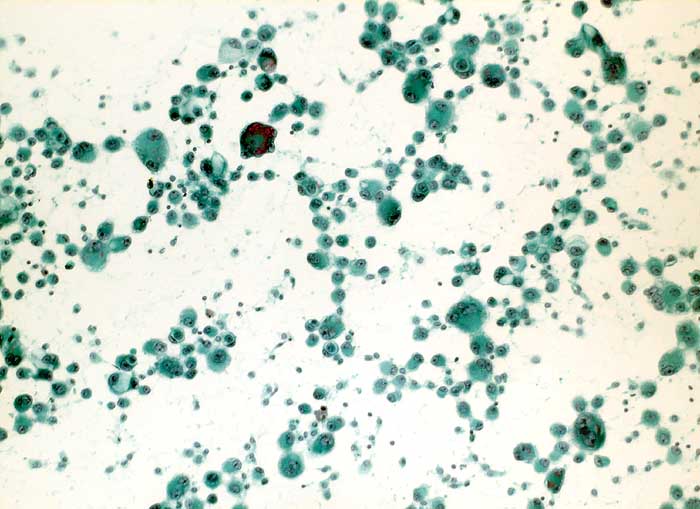

Maligner Pleuraerguss: Adenokarzinom der Lunge

Pleuraerguss Zytologie

Folgendes Antikörperpanel eignet sich für die Bestätigung der Verdachtsdiagnose einer Pleurakarzinose eines primären Bronchuskarzinoms: BerEP4 (Adenokarzinom positiv), TTF1 (Lungen- und Schilddrüsenkarzinom positiv), Calretinin (Mesothelien positiv) und Vimentin (Mesothelien positiv).